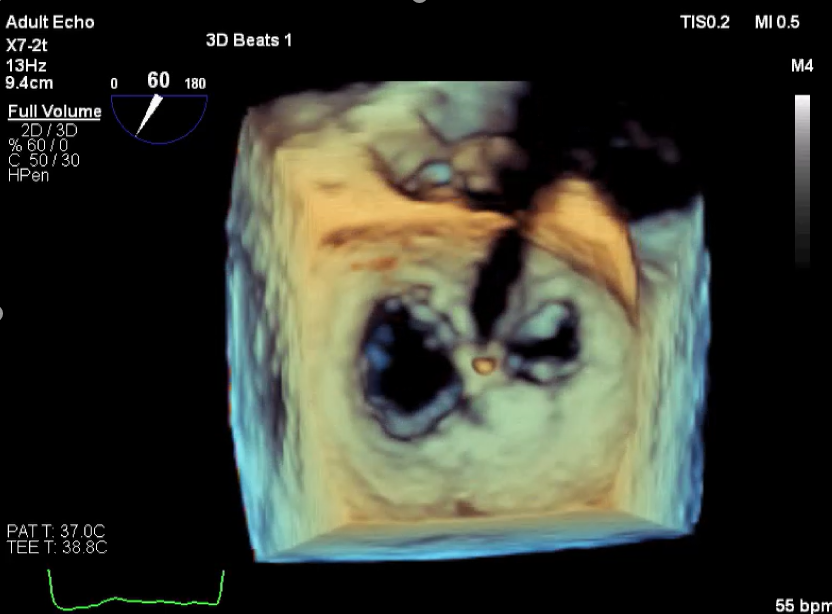

术前超声评估

术前超声诊断

LVOT-color:MR(重度),返流面积11.3cm2

肺静脉血流频谱呈收缩期反向

3D-color MV view:血流主要来源于2、3区

Qlab软件勾画估测瓣口面积约:6.16cm2

TEE LVOT切面返流量评估

TEE 4-Ch view返流量评估

术中超声

确定房间隔穿刺点:靠后

2D视图下测量大鞘长度2cm

3D视图打开夹子

X-plane:下第夹子尝试捕获2区

X-plane:测量前叶长25mm,后叶长14.2mm

X-plane:计算前叶捕获长度8mm,后叶捕获长度7mm

3D视图下观察二尖瓣双孔形态

3D-color:残余少量返流